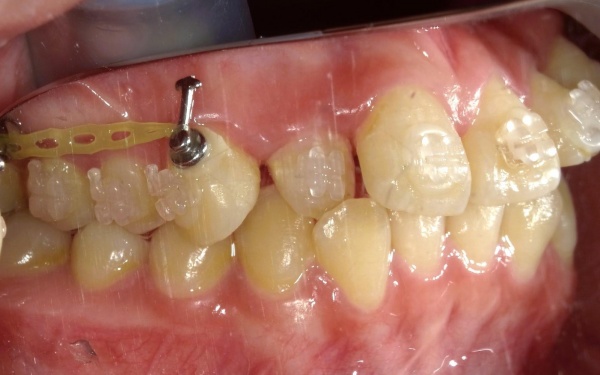

20代女性 抜歯による口元の後退を回避するため、アンカースクリューを用いた歯を抜かない非抜歯治療を行った症例

・歯を後方へ引っ張るための固定源とする矯正用の小さなネジ「アンカースクリュー」を併用し、奥歯を後方へしっかりと動かしながら歯を並べるスペースを作り、前歯が突出しないよう歯並びを改善する

まず、乳歯と親知らずの計5本の歯を抜き、そのあとにマルチブラケット装置を装着します。

上顎の骨にはアンカースクリューを埋め込み、定期的に調整しながら歯を適切な位置に動かしていきました。

治療中画像 治療中画像 治療中画像